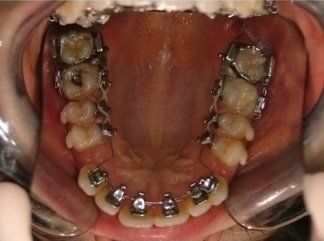

L'idea innovativa di applicare delle maniglie (brackets) sul lato interno dei denti, rivolto alla lingua anziché sul lato esterno rivolto al labbro ed esposto al sorriso, ha fatto sì che questa tecnica venisse denominata “linguale".

I risultati dell’ortodonzia linguale sono gli stessi di quelli ottenuti con gli apparecchi tradizionali, ma a causa della maggiore difficoltà che possono incontrare gli operatori questa tecnica è ancora usata solo da pochi specialisti in Italia e nel mondo.